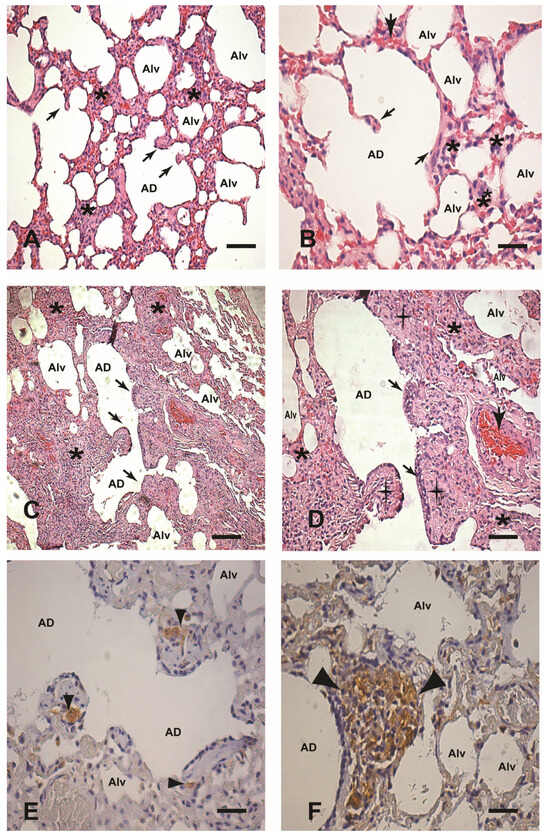

In general, intense chronic interstitial pneumonitis was the main lesion observed, but it was only notable in naturally infected dogs and dogs experimentally infected with the BH401 strain. Indeed, this chronic pathology was minor or absent in the lung tissue sections from dogs experimentally infected with the BH46 strain and in controls. Under microscopic analysis, chronic interstitial pneumonitis was characterized by thickening of the alveolar wall (alveolar septa) as a result of mononuclear cell infiltrates consisting of macrophages, plasma cells, lymphocytes, rare neutrophils, and an occasional eosinophil. This cellular exudate was generally mainly diffuse throughout, mainly into the alveolar septa, but in some cases, mononuclear cells also appeared in patches. In addition, blood vessel congestion (alveolar capillaries) was notably hyperemic. However, there was no alveolar damage or alveolar capillary alterations (except hyperemia) and/or oedema or intra-alveolar inflammatory cells. A chronic inflammatory exudate around the bronchioles was also observed in parallel to the interstitial pneumonitis, but only in the naturally and BH401 experimentally infected dogs (Figure 1A–D). Also, in pulmonary interstitium, under optical microscopy (immunohistochemistry), we found intracellular amastigote forms of Leishmania associated with the inflammatory exudate in all dogs experimentally infected with L. infantum strain BH401 and seven naturally infected dogs (Figure 1E,F). However, we did not find any amastigotes of Leishmania in the lung tissue of dogs experimentally infected with the L. infantum BH46 strain and controls. Thus, we applied PCR assays in these cases. PCR was successful (positive for Leishmania DNA) in four of seven dogs of this group. Otherwise, we found positive results of three more cases out of eleven dogs naturally infected with L. infantum. All controls were PCR-negative. It is important to say that all infected dogs showed parasites in other organs, such as the liver, spleen, and cervical lymph nodes [17].

Figure 1. (AF) Paraffin-embedded lung sections from uninfected dogs (controls) and dogs naturally and experimentally infected with L. infantum (BH401 strain). (A,B) Control dog: (A) Lower magnification showing pulmonary interstitial cells (alveolar wall) (asterisks), 220×. Note the regular pulmonary knob structures (black arrows). (B) Higher magnification showing interstitial cells into the interalveolar septum (asterisks), 440×. (C,D) Naturally infected dog: (C) Lower magnification showing a conspicuous thickness in the interalveolar septum (asterisks) associated with chronic interstitial pneumonitis in comparison to controls, 220×. (D) Presence of an intense chronic cell exudate into the intra-alveolar septum (asterisks); note the thickness of the pulmonary knob structures (black cross), the hypertrophy and hyperplasia of the pneumocytes (black arrows), and the hyperemia (large black arrow), 440×. (E,F) Experimentally infected dog (BH406 strain): Note immunolabeled amastigote forms of Leishmania (in brown) localized in the pulmonary interstitium (arrowheads), 440×. In (F), note the numerous macrophages loaded with immunolabeled parasites in the granuloma formation (large arrowheads), 440×. (AD) Hematoxylin and eosin staining. (E,F) Immunohistochemistry streptavidin–peroxidase method with counterstaining with Harris hematoxylin. Alveolar duct (AD). Alveolus (Alv). Bars (A,C) = 20 µm; Bars (B,DF) = 60 µm.